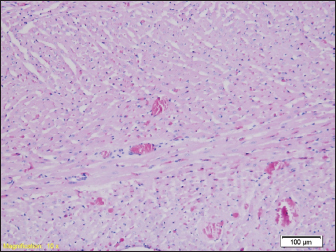

Fig. 5. Blood filling of hepatic sinusoids and centrolobular vein (HE, ×100).

Signs of degenerative changes caused by drowning were found in the liver samples. It is believed that drowning and hypotension during recovery lead to irreversible changes in the organs caused by a lack of oxygen. Similar changes were found in other studies, where the liver showed small but numerous clusters of hyaline bodies in the liver sinusoids (Ikeda et al., 1998).

Our results show signs of overcrowding of hepatic sinusoids with partially ballooned hepatocytes. These results were found in previous studies, where hepatocytes had hydropic degeneration (Ibrahim et al., 2022). The changes that can occur to the organs can largely depend on the type of water in which the drowning occurred, from salt water to fresh water. In our study, rats were drowned in water from the Bosnia River. Upon examination of the heart muscle, we found congested blood vessels, with no signs of degeneration. In contrast to our results, Mahrous et al., found signs of cardiac muscle cell damage after drowning in salt water, which were presented as a greater number of vacuoles in the cytoplasm, a reduced number of nuclei in the cells, and an inflammatory infiltrate, but also edema and congestion of blood vessels as in our results (Ibrahim et al., 2022). Christe et al. (2008) found an enlarged heart on the post-autopsy material, with an increased volume of the right atrium and right ventricle, while the left side of the heart was enlarged in only one person (Christe et al., 2008).

However, studies have shown that there are statistical differences in the number of diatoms in false positive cases and actual drowning cases. Therefore, a comprehensive analysis of multiple organs, rather than just one organ, would be more useful for the diagnosis of drowning. Relatively uniform changes are observed in the liver samples of all groups of rats, which in each sample include a certain degree of congestion, with overcrowding of the centrolobular veins, but also the veins of the portal space, as well as dilation of sinusoids-filled with erythrocytes, while hepatocytes in places show signs of paper degeneration.